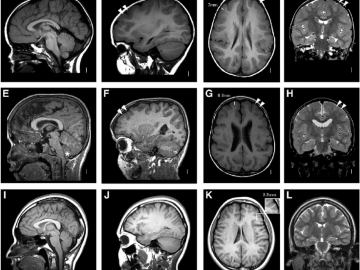

МРТ при условии адекватного выполнения на аппарате с достаточной (1,5–3 Тесла) напряженностью магнитного поля является очень чувствительным методов в выявлении церебральных и спинальных очагов в белом веществе при рассеянном склерозе, которые гиперинтенсивны на T2 и FLAIR, их характерная морфология, паттерн распределения или вовлечение определенных структур позволяют поддержать диагноз рассеянный склероз (см табл. и рисунок). В то же время важно помнить об их неспецифичности и возможности развития очень похожих изменений при многих других заболеваниях. Из практически особенно важных аспектов следует обратить внимание на то, что едва ли не наиболее частая причина дифференциальной диагностики рассеянного склероза по МРТ изменениям — гипоксически-ишемическая болезнь мелких сосудов, особенно у лиц среднего и пожилого возраста, среди которых весьма распространена.

Исходя из этого важно помнить, что из супратенториальных очагов для рассеянного склероза типичны юкстакортикальные очаги (с вовлечением U-волокон), очаги в мозолистом теле и проводящих путях, прилегающих к области тригонума (коллатерального треугольника) и височным рогам боковых желудочков, а из инфратенториальных очагов — на дне четвертого желудочка, мозжечковых ножках, продолговатом мозге, интрааксиальном сегменте тройничного нерва и на пиальной и вентрикулярной поверхности моста (то есть на периферии). Не менее важно обнаружение очагов в спинном мозге, которые для гипоксически-ишемических васкулопатий не характерны, а при рассеянном склерозе часто обнаруживаются в шейном отделе и мозговом конусе.

Рисунок. Типичные для рассеянного склероза изменений на МРТ: одновременное присутствие контрастируемых и неконтрастируемых очагов (А и Б); юкстакортикальные очаги (В); перивентрикулярные очаги (Г), инфратенториальные очаги (Д), очаги в спинном мозге (Е). Собственные наблюдения Хайбуллина Т.И, Гранатова Е.В., Бабичевой Н.Н., Аверьяновой Л.А.